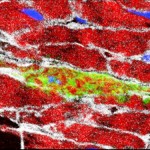

Los científicos en el Grupo de Investigación de Thomas Braun en el Instituto Max Planck para la Investigación del Corazón y del Pulmón han logrado identificar una población de células madre en ratones que juega un papel clave en esta regeneración de las células del músculo del corazón. Los experimentos realizados por los investigadores en Bad Nauheim con ratones genéticamente modificados muestran que las células madre Sca1 en la salud del corazón están involucradas en la sustitución continua de las células del músculo del corazón. Las células Sca – 1 aumentan su actividad si el corazón está dañado, con el resultado de que se forman las células significativamente más nuevos del músculo del corazón.

Dado que, en comparación con la gran cantidad de células del músculo cardíaco, las células madre SCA1 representan sólo una pequeña proporción de las células en el músculo del corazón, la búsqueda de ellas es como buscar una aguja en un pajar.

«También se enfrentan al problema de que SCA1 ya no está disponible en las células como una proteína marcadora de células madre después de que han sido transformadas en células de músculo cardíaco. Para probar esto, tuvimos que ser creativos», dice el líder del proyecto Shizuka Uchida. Los investigadores del Instituto Max Planck modificaran genéticamente las células madre hasta el punto de que, además de la SCA1, se produjo otro marcador visible. Incluso si SCA1 estaba posteriormente no es visible, el marcador todavía podría ser detectado de forma permanente.

«De esta manera, hemos sido capaces de establecer que la proporción de las células del músculo del corazón se originan en células células madre SCA1 que aumentan continuamente en ratones sanos. Alrededor de un cinco por ciento de las células musculares del corazón regenera a sí mismas dentro de los 18 meses», dice Uchida. Por otra parte, los ratones que sufren de enfermedades del corazón provocada por el experimento tenían hasta tres veces más de estas células del músculo cardíaco recién formadas.